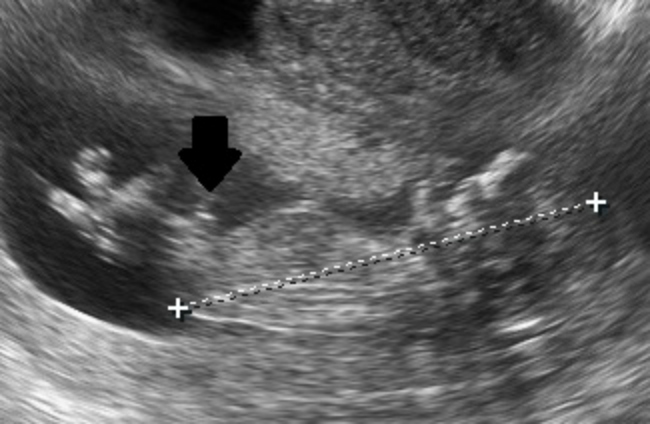

I posted my nub pictures about a week ago, but they were unclear. I thought I saw something! Anyway, I figured out how to post video I have from my ultrasound. I slowed it down because the original was only 4 seconds long. Between the legs of my baby, I think there is a moving nub? It looks different from our baby's legs which are crossed. Like a little stack, I wish I could circle it. Any ideas? I appreciate it!